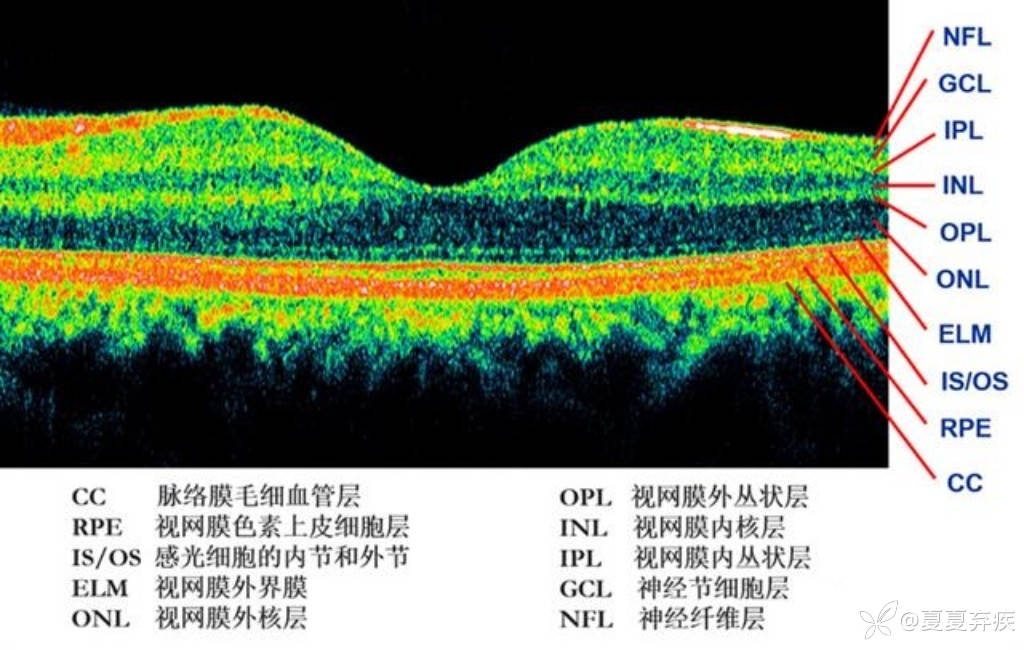

1、正常:黄斑区视网膜各层形态基本可;

2、屈光介质混浊,视网膜各层结构观察不清;

3、黄斑水肿:黄斑区视网膜神经上皮层厚度增加,中心凹正常形态消失,层间可见高反射颗粒/低反射囊胜腔。

4、黄斑板层裂孔:黄斑区视网膜神经上皮层部分连续性中断;

5、黄斑裂孔:黄斑区视网膜神经上皮层全层连续性中断;

6、黄斑前膜:黄斑区视网膜表面可见僵硬条带与之相贴、牵拉隆起,中心凹形态异常。

7、视网膜脱离:黄斑区视网膜神经上皮层与RPE层分离;

8、CN/AMD:黄斑区视网膜RPE层高反射隆起/不规则隆起/形态不平整;

9、黄斑劈裂:黄斑区视网膜层间无反射区,光感受器层反射欠连续,中心凹形态欠佳。

视盘OCT:视神经纤维层厚度增厚/变薄